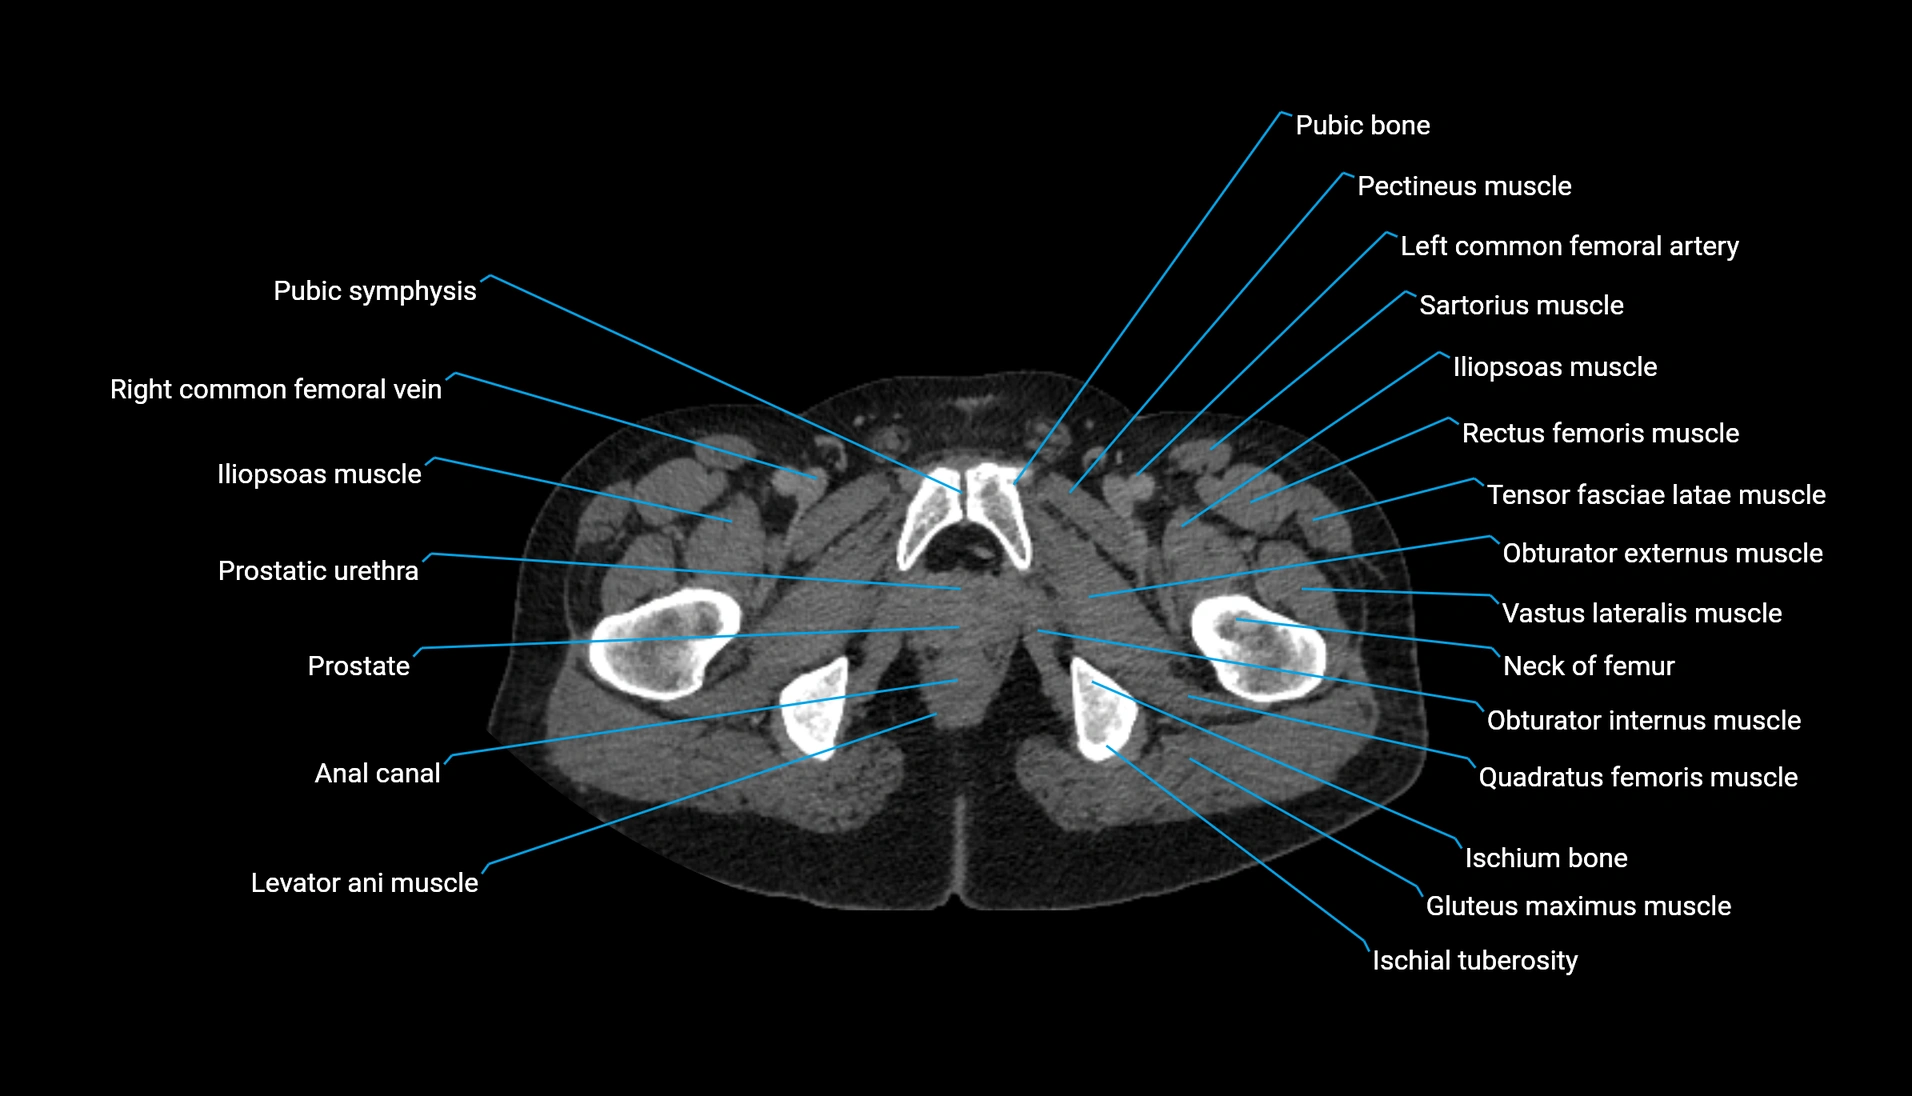

CT Appearance

Non-contrast CT:

-

Demonstrates cortical bone of acetabular rim in excellent detail

Detects fractures, dysplasia, retroversion, or bony overcoverage (pincer impingement)

3D reconstructions used in preoperative hip surgery planning

CT VRT 3D image

CT image